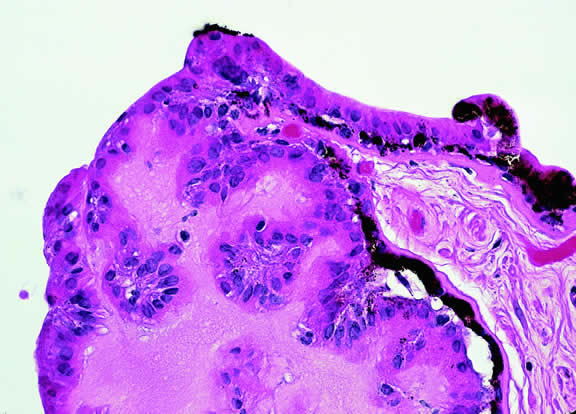

Fig. 5. Ciliary body melanocytoma. Ciliary epithelium covers intensely pigmented tumor. Melanin pigment obscures nuclei. (Hematoxylin-eosin, × 50.)

Most melanocytomas of the optic disc have a feathery margin caused by infiltration of the nerve fiber layer. In approximately one half of cases, a juxtapapillary component in the choroid identical to a choroidal nevus is present.16 Visual acuity is often good, but 30% of patients have an afferent pupillary defect.17 Visual field examination may show enlargement of the blind spot or nerve fiber bundle defects.17 About 15% of optic disc melanocytomas enlarge on follow-up.16 Rare cases of malignant transformation have been reported.18, 19, 20 Central retinal vein occlusion has been reported in a patient with a necrotic optic disc melanocytoma and does not always imply malignant transformation.21 Primary malignant melanomas of the optic nerve head have been reported.22 Retinal pigment epithelial (RPE) adenoma may mimic optic disc melanocytoma.23

Histopathologically, melanocytomas are composed of cells that have abundant quantities of maximally pigmented cytoplasm that often obscures nuclear details, making microscopic assessment impossible11 (see Fig. 5). Bleached sections, which are a requisite for examination, show that the cells have bland nuclei and a low nuclear-to-cytoplasmic ratio (Fig. 6). Nucleoli usually are inconspicuous, but there are exceptions to the rule. Electron microscopic studies also have revealed a second population of spindle cells.15,24 Melanocytoma cells resemble the benign melanocytes found in the uvea of patients with ocular melanocytosis.

Fig. 6. Melanocytoma, depigmented section. Bleaching of melanin pigment discloses cells with bland nuclei and low nuclear-to-cytoplasmic ratio consistent with benign magnocellular nevus. (Bleach, × 250.)